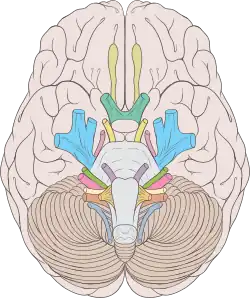

Der Hirnnervenkern des N. trochlearis, der Nucleus nervi trochlearis, liegt im Mittelhirn und schließt sich dem Hauptkern des Nervus oculomotorius kaudal an. Die Fasern steigen vom Trochleariskern in laterokaudaler Richtung ab, ziehen um das zentrale Höhlengrau herum nach dorsal und kreuzen in der Decussatio trochlearis zur Gegenseite, unmittelbar vor ihrem Hirnaustritt. Unterhalb der Colliculi inferiores (bzw. caudales) der Vierhügelplatte und seitlich des Frenulum veli medullaris rostralis (bzw. superioris) tritt der N. trochlearis als einziger Hirnnerv dorsal aus dem Gehirn.

In der Cisterna ambiens des Subarachnoidalraums windet er sich seitlich um den Hirnschenkel (Pedunculus cerebri) an die Basis des Hirnstamms und verläuft hier zwischen der Arteria cerebri posterior und der Arteria superior cerebelli. Etwa in Höhe der Türkensattellehne (Dorsum sellae [turcicae]) durchsetzt er am Rand des Tentoriumschlitzes (Incisura tentorii) die Dura und verläuft in der Seitenwand des venösen Sinus cavernosus. Hier liegt der Nervus trochlearis (N. IV) zwischen dem Nervus oculomotorius (N. III) und dem Nervus ophthalmicus (N. V1).